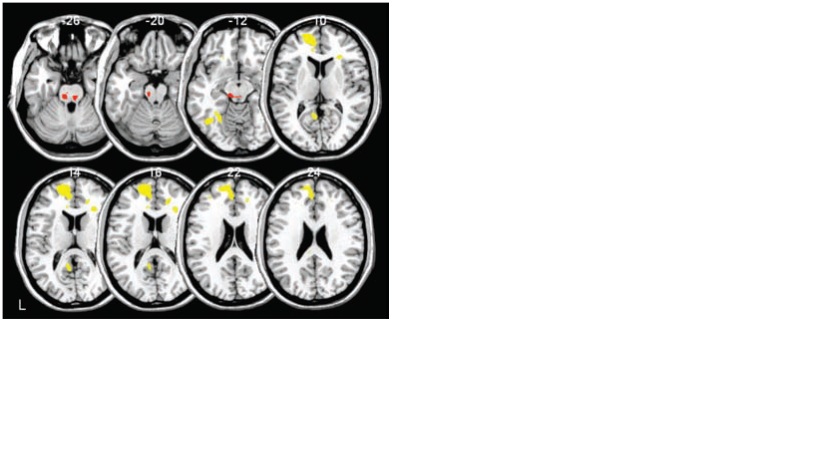

Um grupo de 26 pessoas foi dividido em 2 subgrupos, um deles ficou 35 horas sem dormir e o outro dormiu normalmente. Na figura abaixo as imagens enfileiradas na parte superior pertencem aos que não dormiram e as da parte inferior aos que dormiram. Podemos observar que o grupo que dormiu apresenta, conforme as manchas em amarelo, uma maior atividade do córtex pré-frontal (CPF), aqueles que não dormiram apresentam além de uma menor atividade do CPF uma maior ativação da amígdala (em vermelho).

Qual a importância destas alterções? O CPF é o responsável pelo controle emocional, pela capacidade humana de inibir um impulso emocional, e a amígdala, seria, vamos dizer, o local de onde emergem os impulsos emocionais.